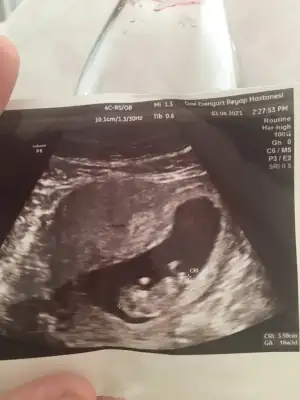

Yapısı erkek gibiBizimkinede bakar mısınız bir doktor kız dedi biri erkek burdada bir ara paylaşmıştım ama şimdide önünde kordon var yine öğrenemedim rica etsem anlayanlar bakabilir mi üç kızım var inşallah saglikli bir erkek istiyorum hayirlisiyla

Teşekkür ederim inşallah nub teorisine göre de erkek demiştiniz bakalım iki hafta sonra ogrencemYapısı erkek gibi

Çok erken en iyi 11 12 13 haftalar olmalı şimdilik kız yönünde ama yanıltabilir